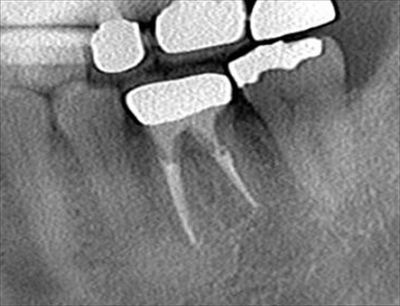

左下第一大臼歯の再根管治療・根管充填を行いました。2018.05.22

未開拓(未治療)であった遠心舌側根管の治療も終えて、前回までに4根管とも根尖まで攻略できました。

本日、垂直加圧根管充填を行いました。

術前には無かった遠心舌側根管の根管充填が現れています。